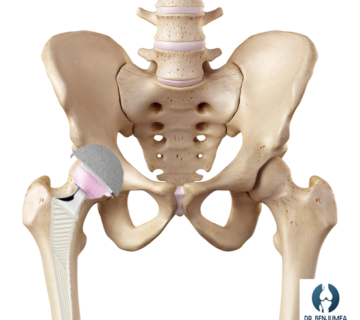

Las prótesis de rodilla pueden ser prótesis total de rodilla: sustituyen a toda la articulación o prótesis unicompartimentales: prótesis parciales que solo sustituyen la mitad de la articulación

La prótesis de rodilla que más se emplean se contienen de 3 a 4 componentes fundamentales, que sustituirán la superficie articular de la tibia, el fémur y la rótula. La parte que sustituye al fémur es llamada escudo femoral, mientras que la tibia es sustituida por el platillo tibial o bandeja tibial. Ambos componentes son de aleaciones metálicas que varían según la marca, pero suelen incluir cromo-cobalto, titanio y entre otros. Entre ambos componentes se coloca un inserto de polietileno que evita que ambas superficies metálicas choquen entre sí. En los casos donde sustituimos también la rótula, colocamos una cuarta pieza: el botón rotuliano de polietileno. Existen prótesis con aleaciones hipoalergénicas indicadas en aquellos pacientes con alergia a metales.